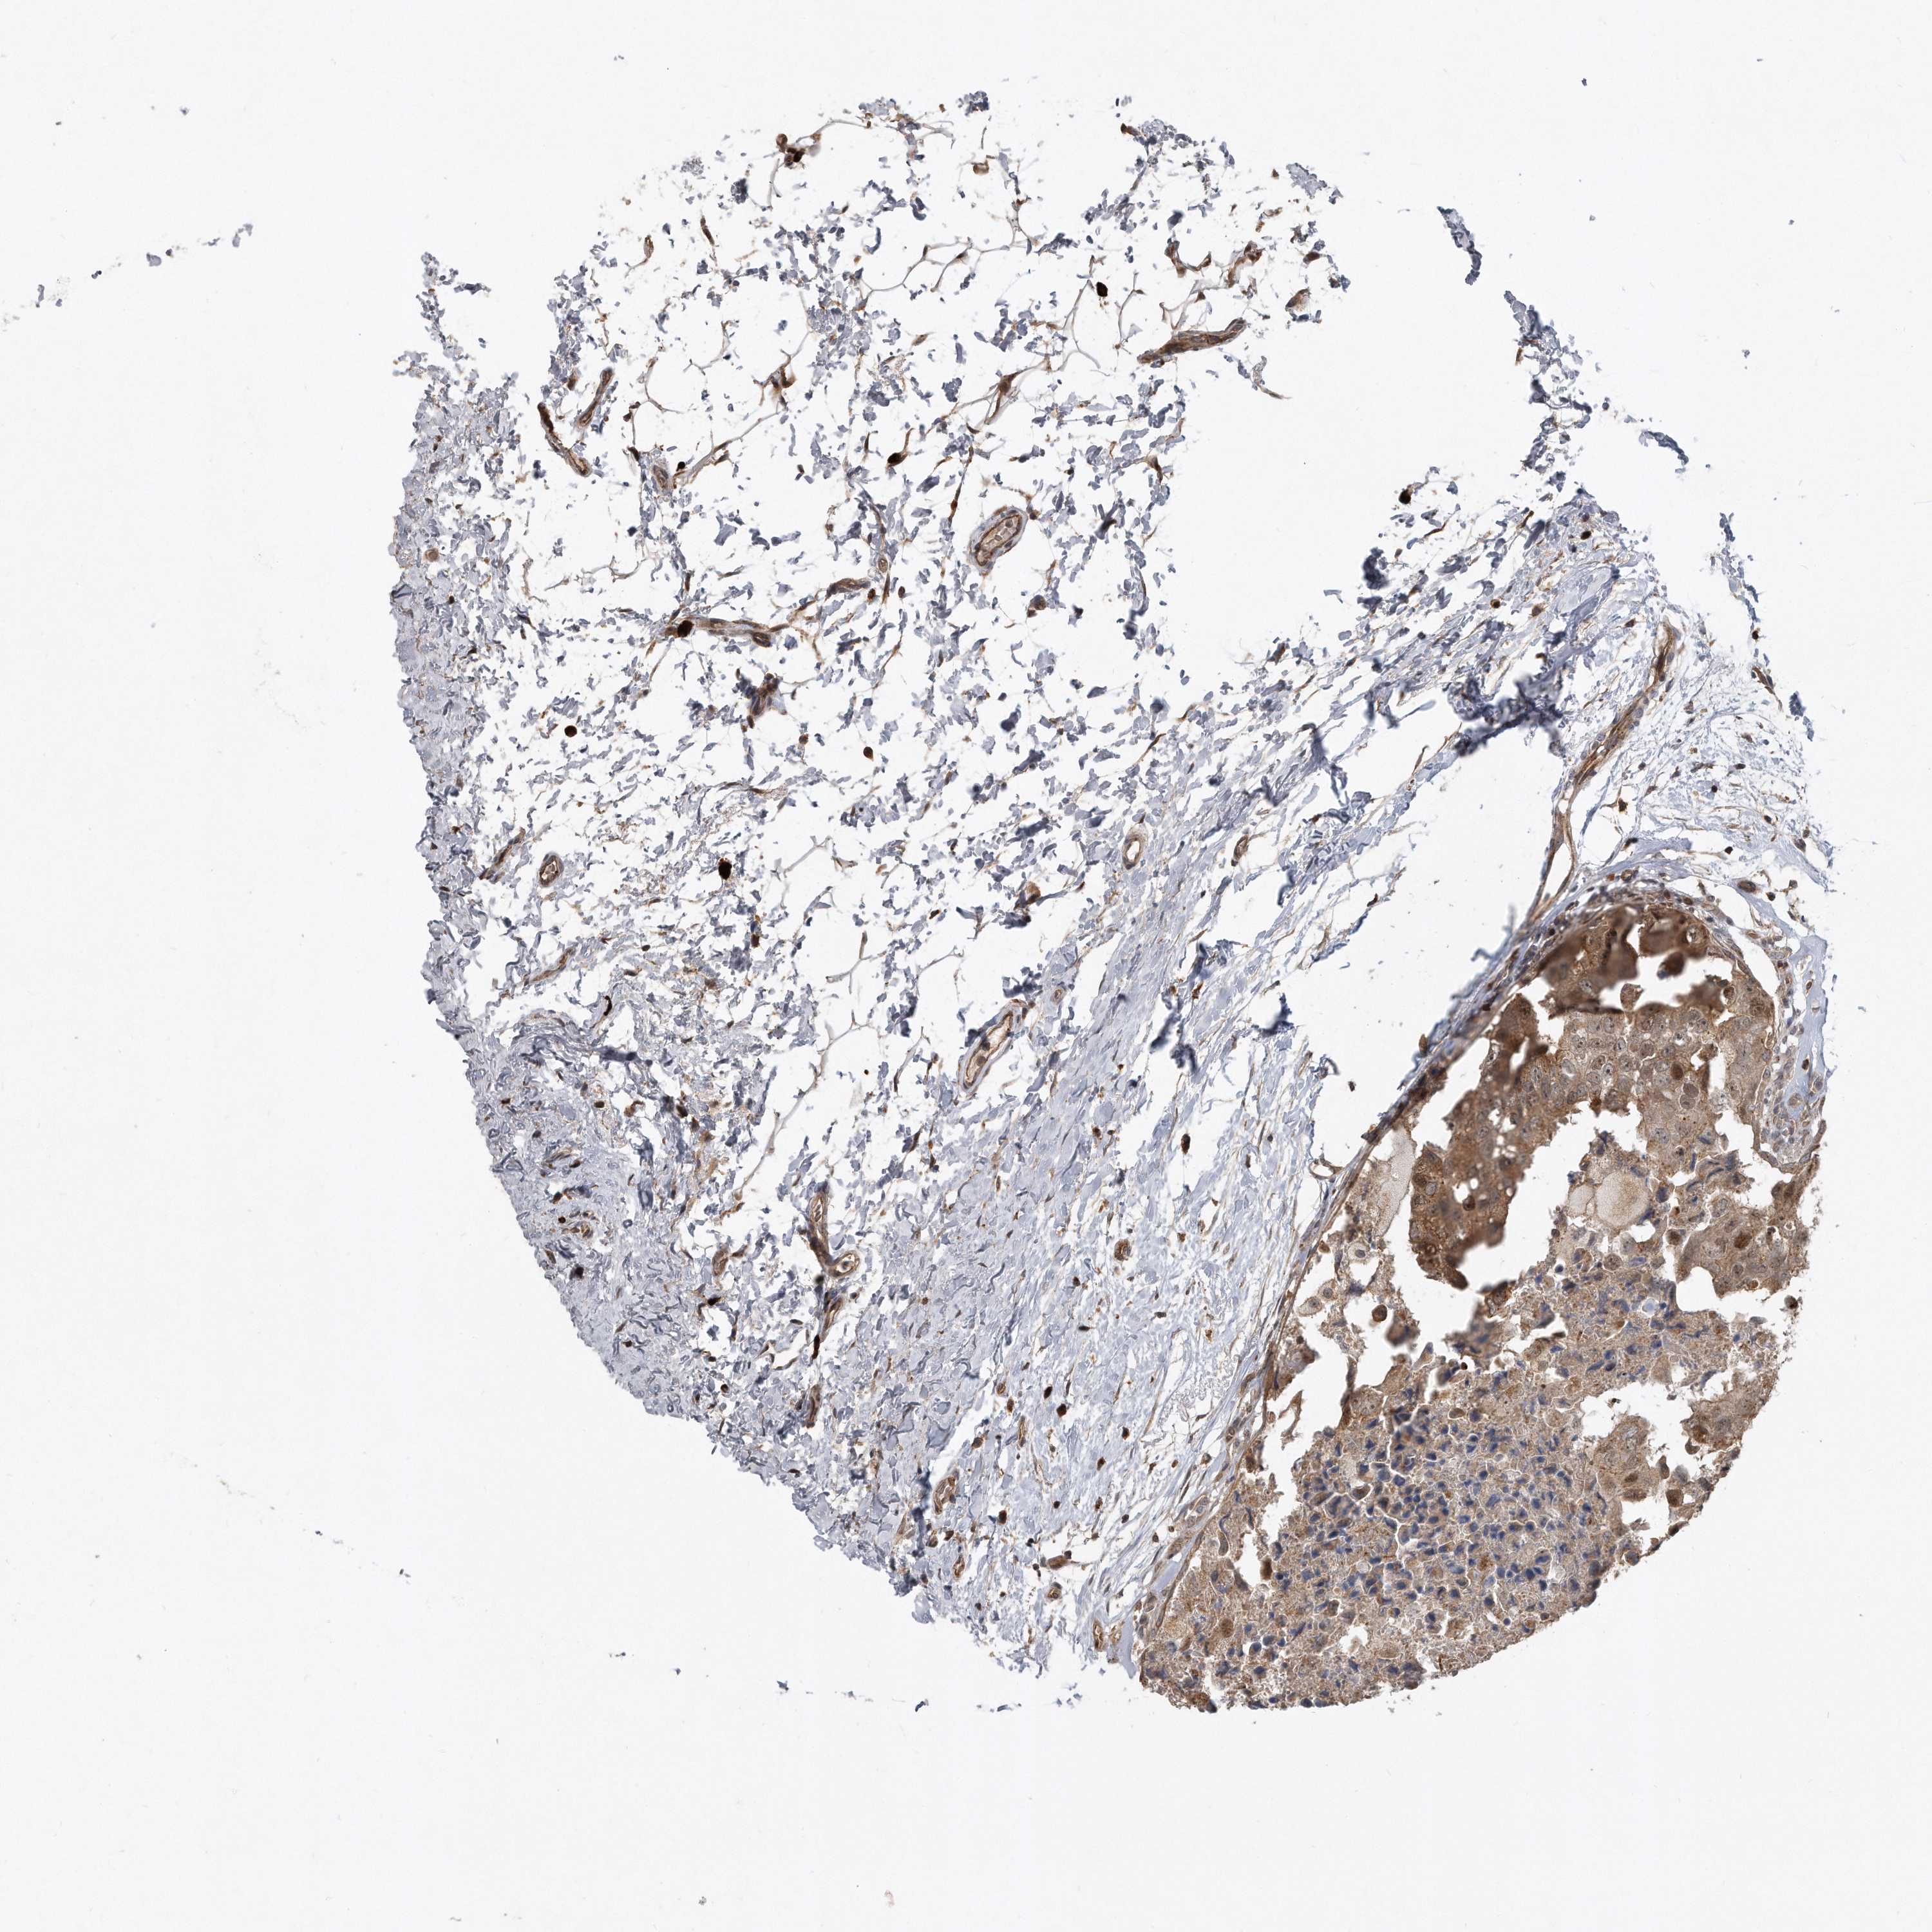

CANCER BREAST CANCER Show tissue menu

BRCA TCGA BRCA VALIDATION PROTEIN EXPRESSION